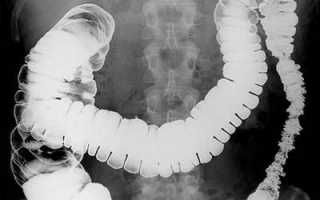

Без введения в организм контрастного вещества рентгеновские лучи легко проходят через мягкие ткани и полости пищеварительной системы, формируя нечеткое изображение.

Высокомолекулярная взвесь бария поглощает поток Х-лучей, и, заполняя весь просвет пищеварительной трубки, подобно слепку, четко вырисовывает «портрет» ЖКТ на экране. Такая «профессиональная фотосессия» позволяет безошибочно рассмотреть положение, форму, структуру, тонус и сокращение стенок (перистальтику) полых органов.

Например, при первых глотках взвеси бария, в позе пациента стоя, отслеживается движение контраста по пищеводу: делается оценка его формы, размера и моторно-эвакуаторной функции.

Контрастное исследование позволяет обнаружить большинство тяжелых заболеваний ЖКТ на ранних стадиях патологических изменений.

Рентгеноскопия желудка с барием показывает:

- инородные тела в ЖКТ;

- болезни пищевода (сужения, выпячивание стенки (дивертикул), новообразования, варикозное расширение вен и др.);

- заболевания желудка и двенадцатиперстной кишки (воспалительные процессы, язву, рак, нарушения всасывания и перистальтики и др.);

- патологии кишечника и других органов.

Для повышения информативности исследования снимки делают в вертикальном, боковом и горизонтальном положениях пациента.